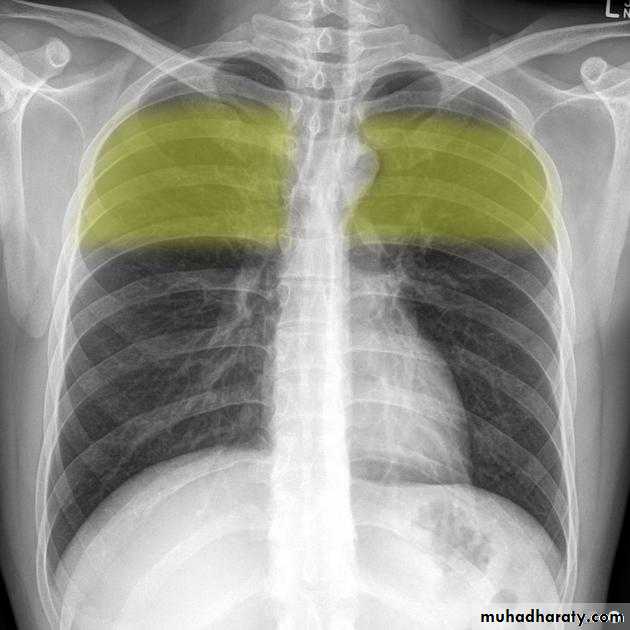

Normally there are 2-10cc of fluid in the pleural spaceWhen >75cc accumulate, the posterior costophrenic (CP) sulci, seen on the lateral film, become blunted

When 200-300cc accumulate, the CP sulci on the frontal film become blunted